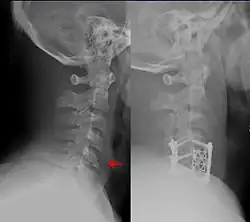

Due to their side-effects, backboards should be removed as soon as possible, even before imaging.[6][7] It is also recommended to remove cervical collars as soon as possible.[6] If patients require ongoing cervical spine precautions, they should be switched to an adjustable cervical collar such as a Miami J collar[6] or halo-gravity traction device for long-term immobilization.[12]

Cervical Spine Clearance

There are two main algorithms, the Canadian C-spine rule and NEXUS, which are used to decide who requires cervical spine imaging via CT scan[6] after blunt trauma, and who can be cleared without imaging.[4] The Canadian C-spine rule appears to have greater sensitivity and specificity (i.e. fewer false positives and false negatives).[17] However, following either rule is reasonable.

If the chosen decision rule (NEXUS or Canadian C-spine) is negative, or if cervical spine imaging is negative, the cervical collar can be removed if the patient does not have significant midline tenderness and can move the neck 45 degrees to both sides.[6] If a patient cannot do both, the collar should be replaced and additional imaging or follow-up should be pursued depending on facility guidelines.[6]

Methods

There are multiple devices that can be used in addition to avoiding maneuvers or activities that move the spine.[8][18] Long-term cervical spine immobilization in patients with cervical spine fracture who did not undergo surgery can be performed using a long-term cervical collar (Miami J,[6][8] Philadelphia,[8] or Aspen[8]) or halo traction device.[8][12] When using a traction device such as the halo to hold the spine in place while it heals, this is called closed reduction, as opposed to a surgery which is termed open reduction with internal fixation (ORIF).[18] In general, the halo traction device is preferred for unstable fracture, while the cervical collars are used for neck sprain, stable fracture, or after surgical fixation.[8] Soft cervical collars do not restrict head movement and are more so used for comfort.[8] The sternal occipital mandibular immobilizer (SOMI) can also be used to provide support for cervical spine sprain, stable fracture, or postoperative support.[8]